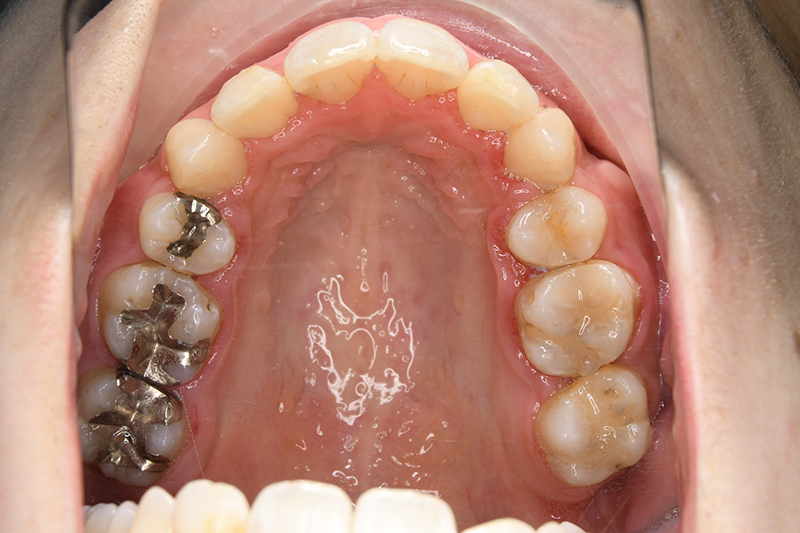

動的治療終了時

FP・IOP

口腔内所見 over jet 11.5mm、over bite 5.5mm、右側臼歯関係Full ClassⅡ級、左側end onⅡ級、上顎顎歯列はテーパー型であり、上顎中切歯は押し出されるように大きく唇側傾斜していた。下顎前歯部は叢生を呈しており、左下5は歯冠長が短く半埋伏していた。

批評・予后 上顎前歯の可及的な後退と臼歯関係のⅡ級を保つためにアンカレッジコントロールはmaximumとしTADを使用してスライディングメカニクスにて前歯遠心移動を行った。また下顎はリンガルからのアプローチであったためその特性を生かし、臼歯のアップライトを速やかに達成して左下5の配列も予定通り行えた。また大幅な前歯の後退に伴い、軟組織の大幅な改善が認められたように思う。